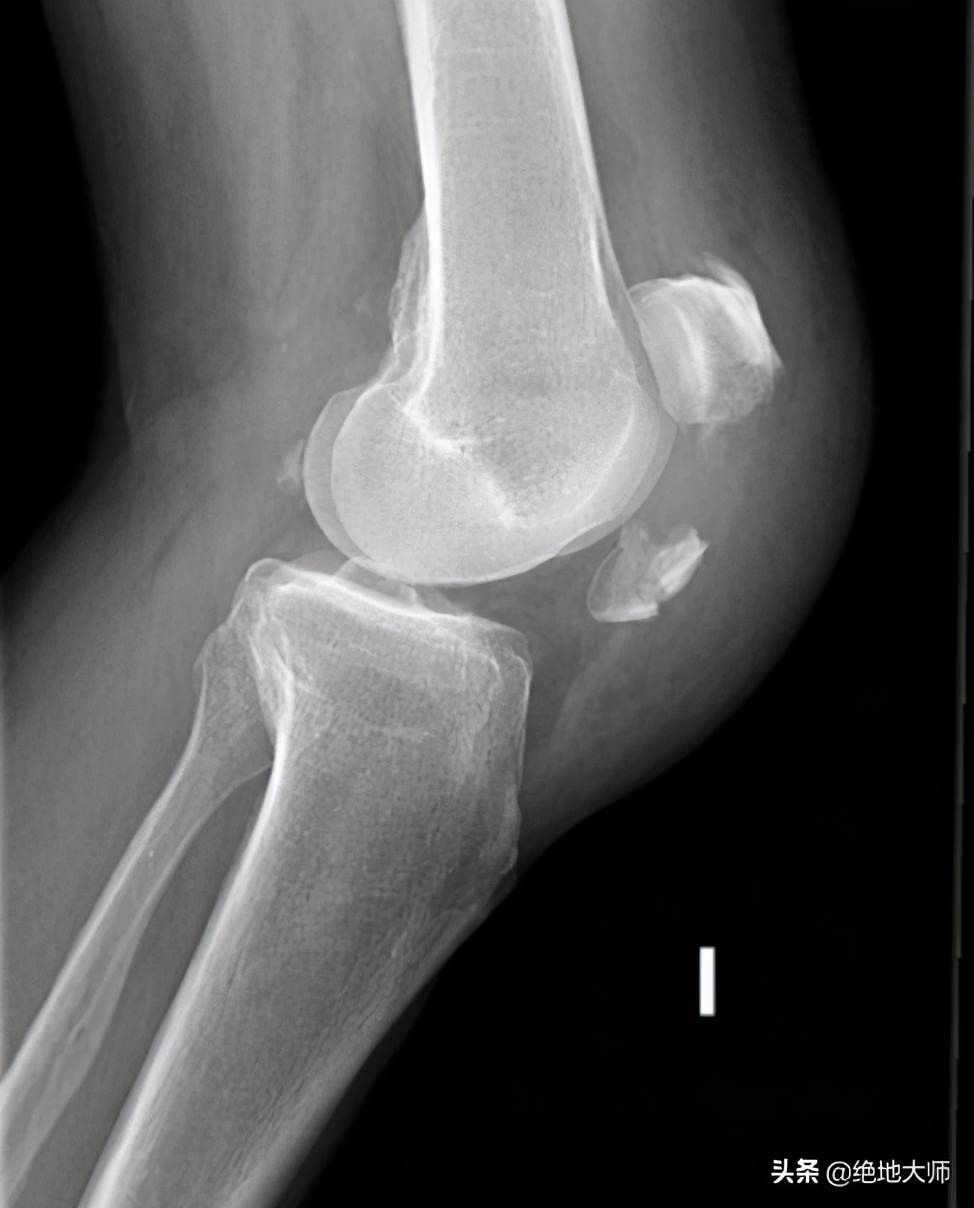

13. TRAUMATIC KNEE PAIN: FRACTURE 创伤性膝痛:骨折(髌骨)

14. TRAUMATIC: PATELLAR DISLOCATION 创伤性:髌骨脱位

15. PATELLAR DISLOCATION ON X-RAY 髌骨脱位X线

16. TRAUMATIC KNEE PAIN: LIGAMENT TEARS 创伤性膝痛:韧带撕裂